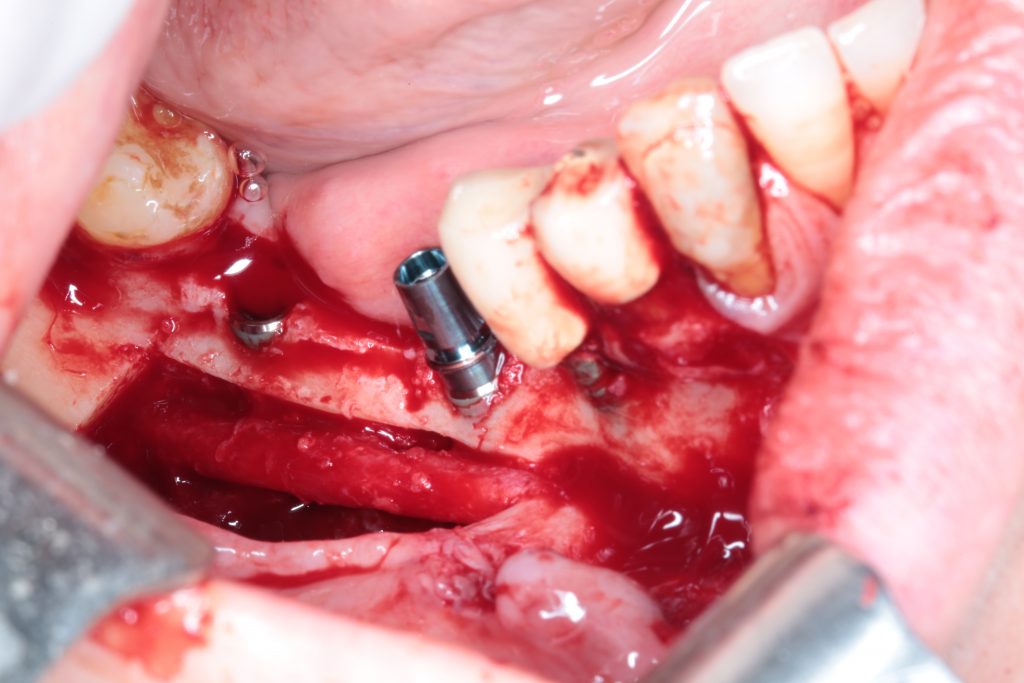

A bone block is harvested from the retromolar area and then split into two very thin bone blades. These blades will be used to restore the missing cortical walls.

Autogenous from chips, obtained with a safe-scrapper like this one, and a bone crusher, will be placed in the space created by those two thin bone blades.

The whole procedure is performed, if possible, through the already explained tunnel approach.

- Sinus lift + Bone augmentation

- Implant Placement + Horizontal Augmentation

- Nerve Lateralization + Bone Augmentation